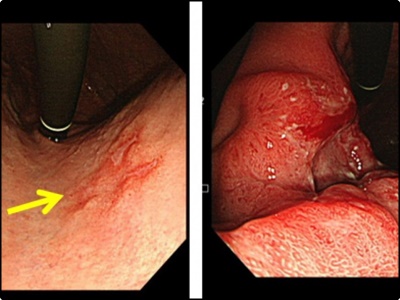

위산 분비가 감소하면서 동시에 소화기능이 저하되면 위 점막에 있는 세포가 변형을 일으키게 됩니다. 그리고 소화기능 저하라는 초기증상으로 나타나게 됩니다. 이는 위암 발생 위험도가 6배나 높습니다. 그리고 위축성 위염이 된 위는 정상인의 위로 회복이 불가능합니다.

하지만 위암으로 발전하지 않게 하도록 연속적인 관리가 필요합니다. 때문에 정기적으로 꾸준히 위내시경 검사를 하는 것이 중요합니다. 때문에 위암을 미리 예방하기 위해서는 나트륨 과다섭취를 피하는 것이 좋습니다. 가능하면 위벽을 자극하지 않도록 해야만 합니다. 위가 자극을 받게되면 위궤양을 일으키고 암세포를 생성하게 됩니다.